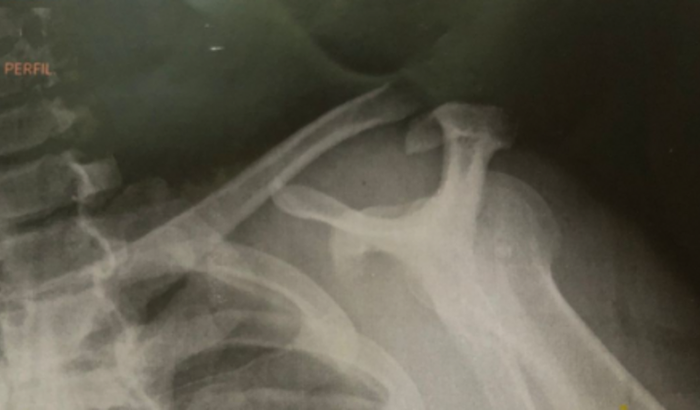

Eu sou Fabio Nascimento Lourenço eu criei está vaquinha para arrecadar uma quentinha pra fazer a minha cirurgia clavícula direita e estou precisando de um valor de 2.500 reais para fazer a cirurgia pois já faz 15dias que sofro com fortes dores na clavícula direita vim fazer a cirurgia pelo SUS mas no momento não tem material pra fazer estou aguardando chegar e no momento estou impossibilitado de pagar uma clínica particular e também manter a minha família pois vou ficar afastado das atividades trabalhista por um período de 90 dias e vou ter que ficar pelo INSS mais como todos sabem que a burocracia é grande pra um pai de família conseguir um benefício por tanto assim agradeço a todos que poderem mim ajudar com qualquer quantia e q Deus abençoe cada um de vcs em nome de Jesus Cristo